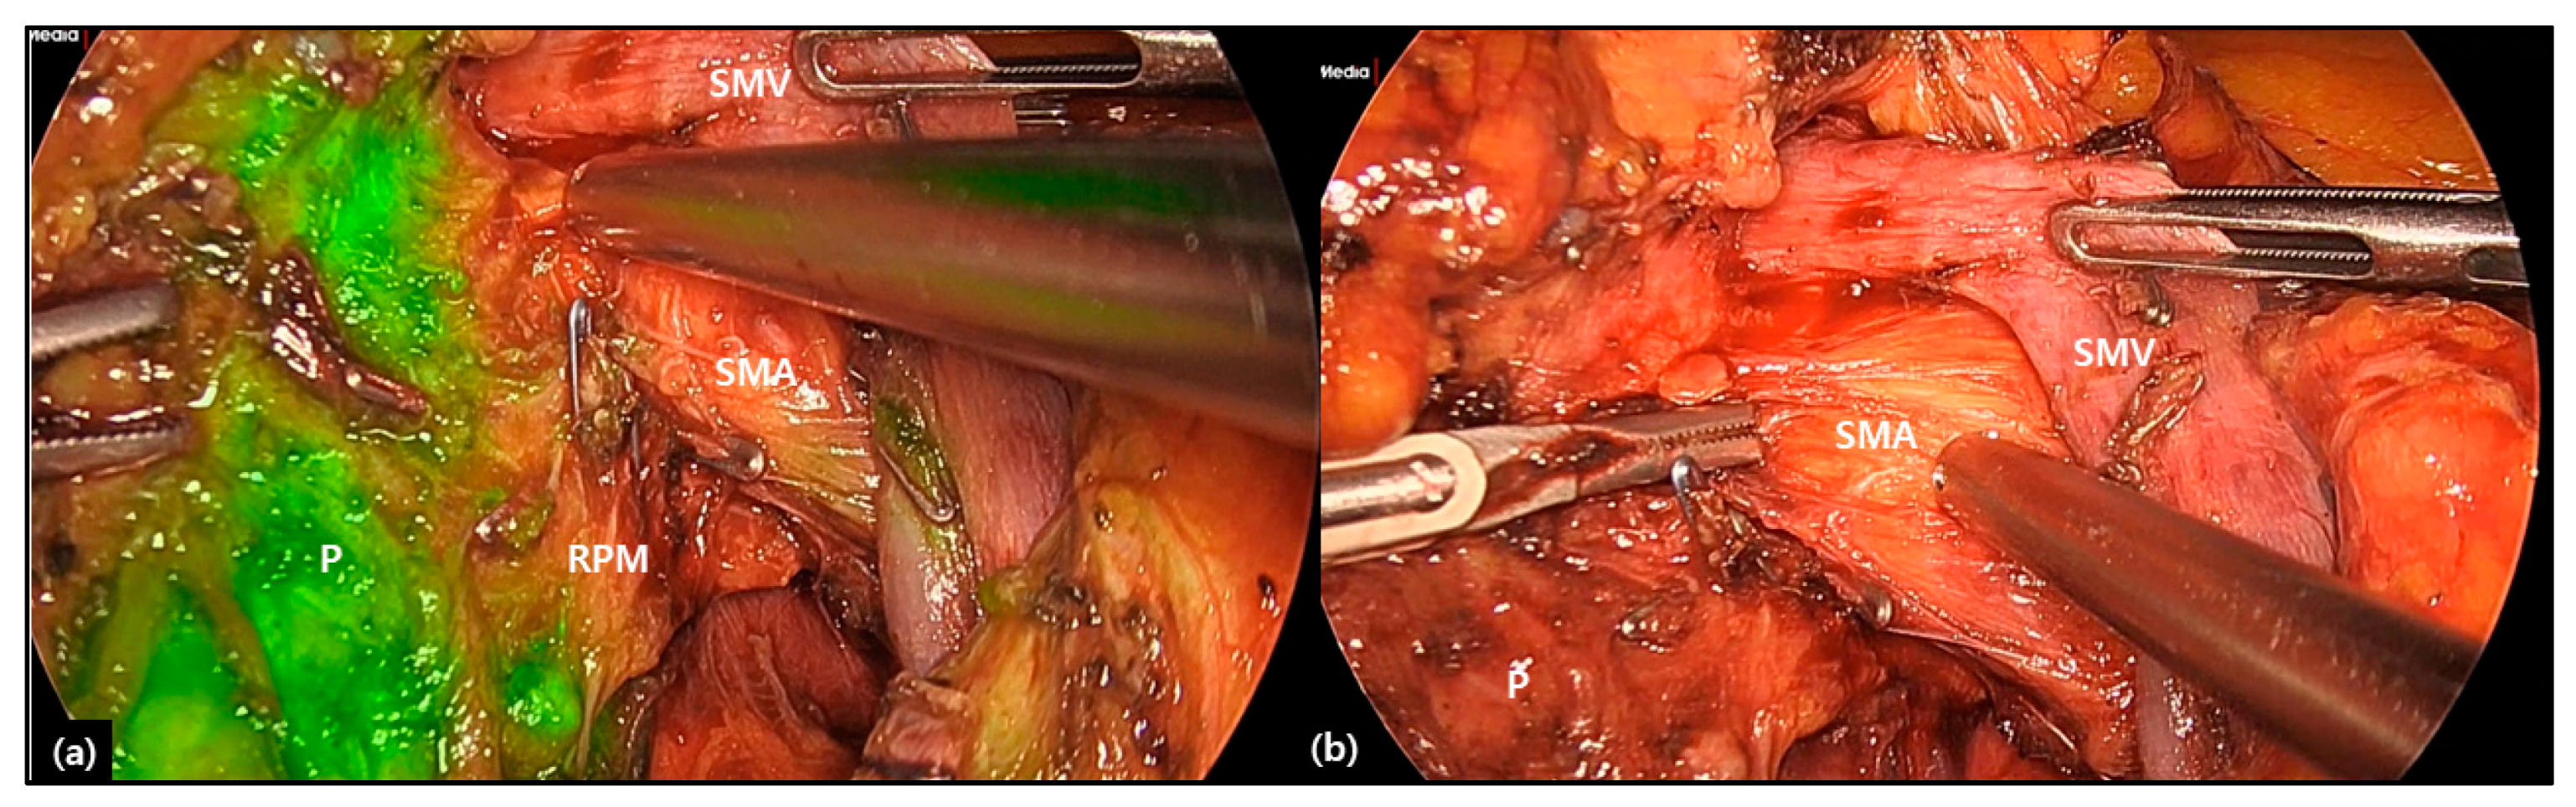

- Rho, S.Y.; Kim, J.S.; Chong, J.U.; Hwang, H.K.; Yoon, D.S.; Lee, W.J.; Kang, C.M. Indocyanine Green Perfusion Imaging-Guided Laparoscopic Pancreaticoduodenectomy: Potential Application in Retroperitoneal Margin Dissection. J. Gastrointest. Surg. 2018, 22, 1470–1474. [Google Scholar] [CrossRef]